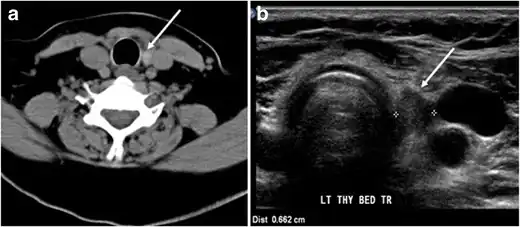

Fig. 15. A 33-year-old female patient who presented with neck swelling and pain and was later diagnosed with Hashimoto's thyroiditis. an Axial enhanced CT scan of the neck demonstrates minimal diffuse enlargement of the thyroid gland, especially the isthmus (white arrow). b Transverse greyscale ultrasound of the neck demonstrates heterogeneously enlarged thyroid and thickened isthmus, measuring 8.6 mm.[1]